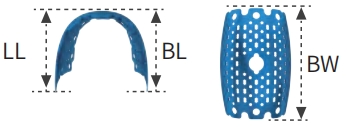

H Type

-

Proximal Width: —

-

Buccal Width (BW): 20 mm

-

Buccal Length: 11 mm

-

Lingual Height: 11 mm

-

Thickness: 0.2 mm